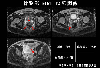

A case of a rectal malignant melanoma with a stalk.

MRI